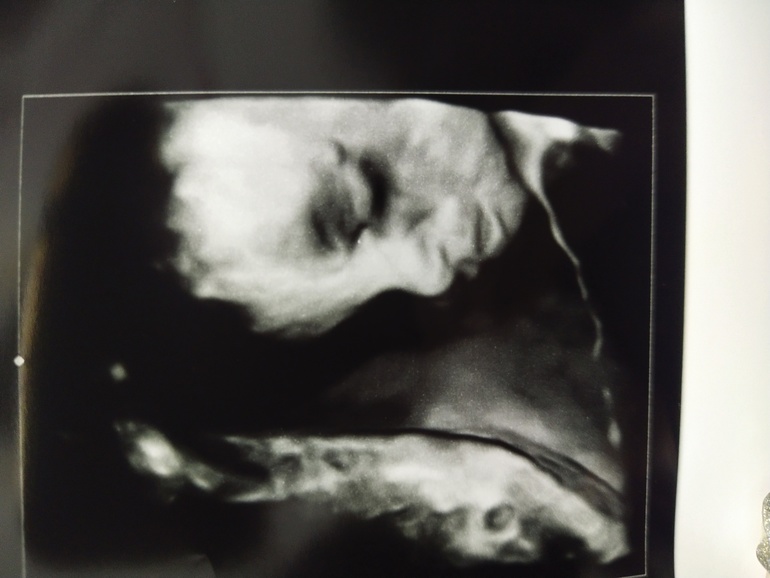

И пупсик мой🥰

Блин, как красиво вышел глазик у человека) фото прям нарисованный портрет)